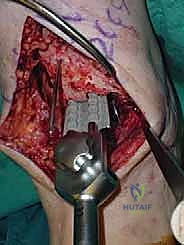

4. وضع أدلة القطع (Jig Placement and Alignment)

تعتمد دقة الجراحة على المحاذاة الصحيحة. يتم استخدام أجهزة توجيه متطورة (Jigs) تثبت على عظمة الساق باستخدام دبابيس معدنية. يتم التحقق من صحة الزوايا والمحاور باستخدام جهاز الأشعة السينية المباشر داخل غرفة العمليات (C-arm Fluoroscopy). يضمن الدكتور هطيف أن يكون القطع موازياً للأرض تماماً عند وقوف المريض.

5. القطع العظمي الظنبوبي (Tibial Bone Cut)

باستخدام منشار جراحي دقيق التذبذب، يتم إزالة شريحة رقيقة جداً (بضعة مليمترات) من السطح السفلي التالف لعظمة الظنبوب. يتم القطع بحذر شديد لتجنب إصابة الأوتار الخلفية أو الأوعية الدموية.